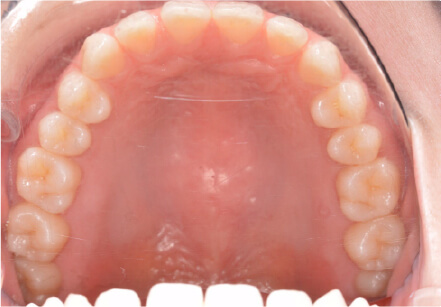

叢生の症例

17歳

女性

相談内容

カウンセリング・診断結果

治療内容・方法

全額アライナー矯正

術後の経過・現在の様子

クリアライナー使用

治療のリスク

痛み・歯根吸収・歯肉退縮・虫歯・後戻り

費用・治療期間

715,000円、2年10ヶ月